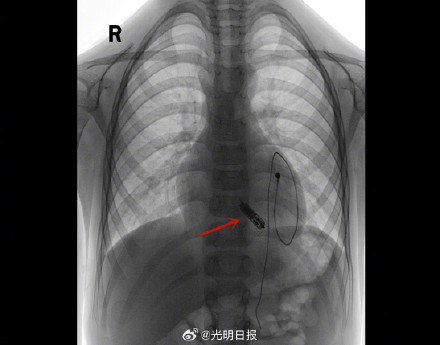

9月4日,6歲的浩浩(化名)從武漢亞洲心臟病醫院康復出院,成為國內植入無導線起搏器年齡最小的患者。浩浩因感冒引發暴發性心肌炎,四年前接連實施了兩次起搏器植入術,過程波折不斷。近日,媽媽帶浩浩到武漢亞洲心臟病醫院成功實施了第三次起搏器植入術。這次植入的是一枚重量僅2克、大小如“膠囊”,目前世界上最小的無導線起搏器。據介紹,無導線起搏器將在浩浩體內工作長達10-15年,未來可以繼續植入新的無導線起搏器,也可更換傳統起搏器。(光明日報全媒體記者張銳、王建宏、嚴德勇)